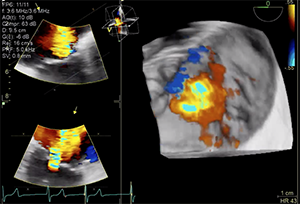

The patient’s left ventricular (LV) systolic function was mildly reduced (LV ejection fraction, 40%–45%), and he had a dilated right ventricle with mild systolic dysfunction based on standard normal ranges (Figure 1 and Figure 2). His right ventricular (RV) systolic pressure was estimated to be 56 mm Hg, as assessed by echocardiography. The results of right heart catheterization showed a pulmonary capillary wedge pressure of 19 mm Hg (V wave to 28 mm Hg), pulmonary artery pressure of 50/14 mm Hg (mean, 29 mm Hg), RV pressure of 50/14 mm Hg, and right atrial pressure of 15 mm Hg (V wave to 20 mm Hg).

Transthoracic and transesophageal echocardiography (TEE) confirmed severe functional TR due to annular dilation associated with RV and right atrial enlargement. Mild leaflet tethering, predominantly septal, was also appreciated. The coaptation gap was < 10 mm and the jet origin was predominantly central with extension toward the anteroseptal commissure. Image quality in both transesophageal midesophageal and transgastric windows were good (Videos 1–5).

Dr. Taramasso: The quality of TEE is really high, and the short axis of the tricuspid valve shows an anteroseptal location of the jet with an acceptable coaptation gap, which is ideal anatomy for edge-to-edge repair. Both MitraClip and Pascal have independent grasping that could be helpful to catch the septal leaflet, which is tethered. Because the annulus is dilated, annuloplasty could be also a good choice.

Dr. Hahn: The current images suggest a relatively small coaptation gap, although the severity of TR is likely “massive.” In the setting of normal RV function, a number of devices could be used, including an annular device (Cardioband) or leaflet device (TriClip [Abbott] or Pascal). These patients could also be treated with an orthotopic replacement device, but less is known about these devices.